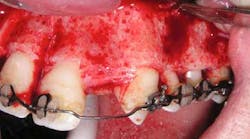

The following case study shows a Caucasian male, age 15 at the beginning of treatment. He had a peg lateral incisor No. 7 and was congenitally missing tooth No. 10. The treatment plan consisted of positioning tooth No. 7 for a veneer and opening space for an implant to replace tooth No. 10. After 30 months of orthodontic treatment had elapsed, there was still insufficient room for implant placement. There was sufficient room for the crown of No. 10, but the roots of teeth Nos. 9 and 11 were still too convergent to allow implant placement. The patient was leaving for college soon and was anxious to have treatment completed. The decision was made to have a periodontist do a corticotomy surgery to accelerate the tooth movement.

Corticotomy surgery was done and distal root movement was initiated on tooth No. 11 using a lever arm and elastic power chain. Root divergence was accomplished in eight weeks, and implant placement was accomplished at that time. The occlusion was detailed and orthodontic appliances were removed a short time later.